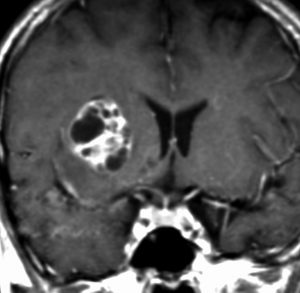

神経下垂体ジャーミノーマと大脳基底核成熟奇形腫

neurophypophyseal germinoma with basal ganglia mature teratoma

12歳の男児が尿崩症で発症しましたが,7ヶ月間診断がつかずに低ナトリウム血症による全身痙攣を生じました。下垂体と右被殻の2箇所に腫瘍があり,AFP 33ng/ml, HCG-beta 1.0mIUと上昇がみられました。神経下垂体の生検術でgerminomaの診断であったために化学療法が開始されました。CPA, VP-16, CDDP, VCRの併用化学療法に,MTXの髄腔内注入が2回でした。なぜこのような乱暴な化学療法を行なったのかは不明です。当然ですが,下垂体のgerminomaは左側のように消失しました。

でも化学療法中に,右大脳基底核にあった腫瘍が増大して,左のMRIのように脳浮腫も悪化しました。この時点で患者さんが転院してきました。腫瘍マーカーは陰転していて,どう見ても奇形腫が化学療法によるparadoxical responseを生じたものでした。ジャーミノーマが消えて奇形腫だけ増大するという現象です。

まず手術で全摘出して,成熟期奇形腫の病理診断を確定しました。それからICE化学療法を2コース加えて,脳脊髄照射 24Gy12分割を行いました。

大脳基底核に胚細胞腫瘍がある場合には全脳照射が基本ですが,なぜ脊髄照射を加えたかということには絶対の根拠はありません。治療前のAFPがやや高く若干の播種性格を有する未熟奇形腫が手術前に消失していたかもしれないという可能性を考えたことと,発症が12歳ですから脊髄照射を24グレイ加えても重篤な遅発性障害が生じないと判断したからです。